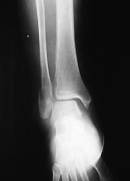

【スライド8】

17

48日再度X線撮影(図9、10)。医師のX線写真の結果報告により骨の位置にほぼ問題がないと判断する。